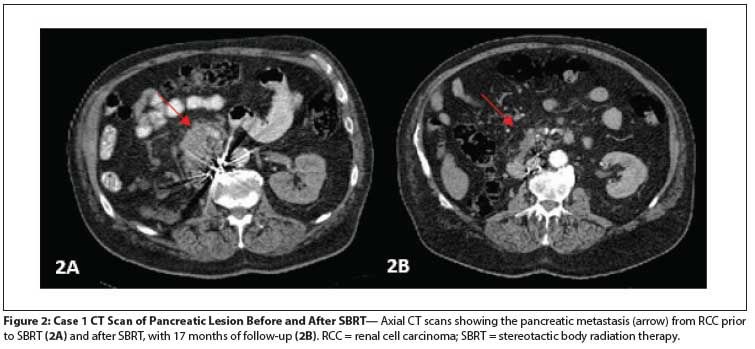

Figure 2: Case 1 CT Scan of Pancreatic Lesion Before and After SBRT

His pancreatic metastases had decreased from 3.8 × 7.2 cm at the start of pazopanib therapy to 2.7 × 7.1 cm at the time of pazopanib discontinuation. He had no clear evidence of active metastatic disease at that time, and because of his poor tolerance of systemic therapy, he was evaluated for stereotactic body radiation therapy (SBRT) to the pancreatic tumor. He was treated with SBRT to the head of the pancreas, 2,500 cGy in 5 fractions, 500 cGy per fraction, given daily (Figure 1A). He tolerated the SBRT well, without any adverse events. Systemic therapy was not restarted.

Seventeen months after the SBRT was completed, his pancreatic lesion had decreased in size to 1.1 × 2.3 cm, with decreased enhancement (Figure 2). The patient had minor intermittent back pain, mainly due to exercise; the pain was not believed to be related to the SBRT. Thus, with 17 months of follow-up, the treated pancreatic lesion had not progressed, and the patient was without symptoms.